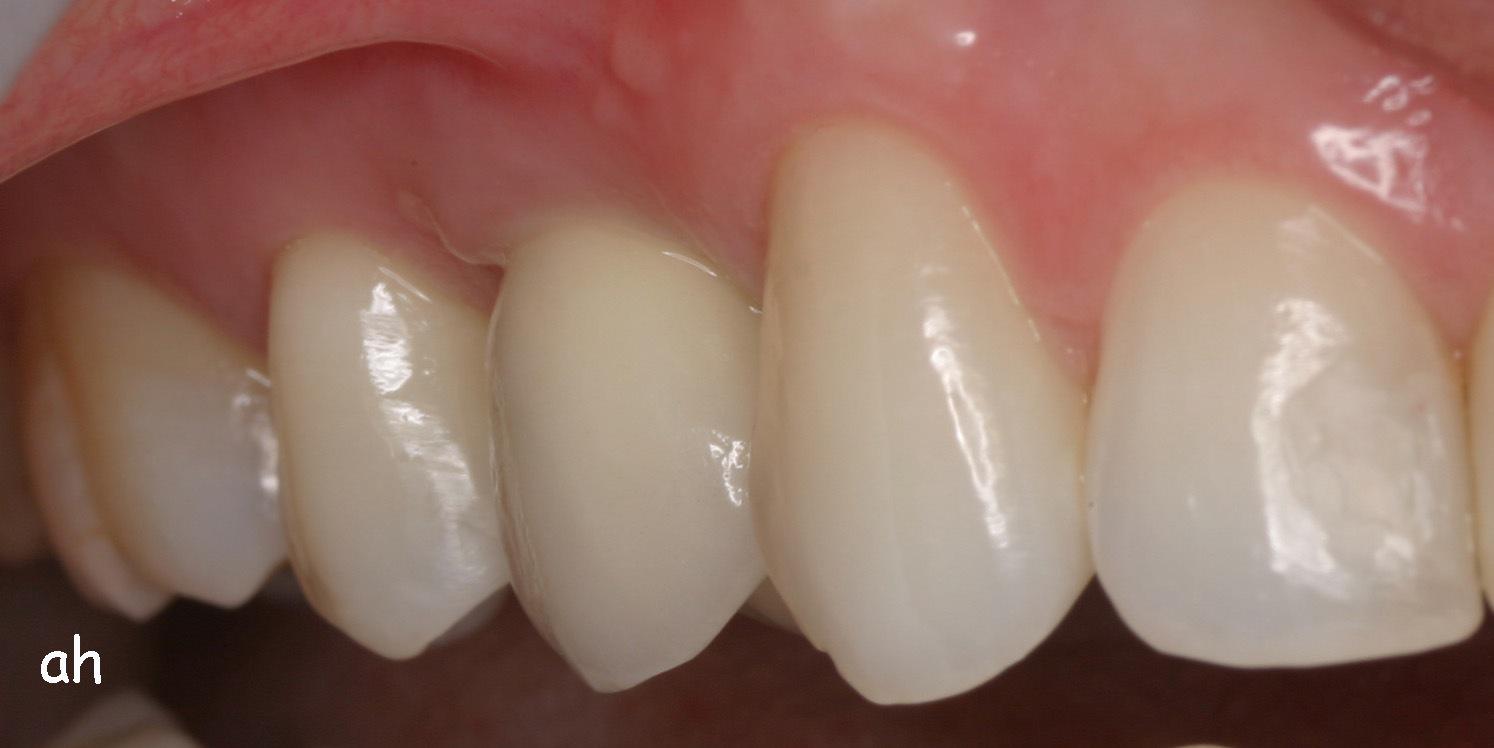

Exemple 3: Un implant à la place d'une incisive latérale supérieure droite. Sur cette image on voit le moignon en titane qui est vissé sur l'implant.

Exemple 3: Puis sur ce moignon, la couronne en céramique est scellée.

Exemple3: La couronne en place.